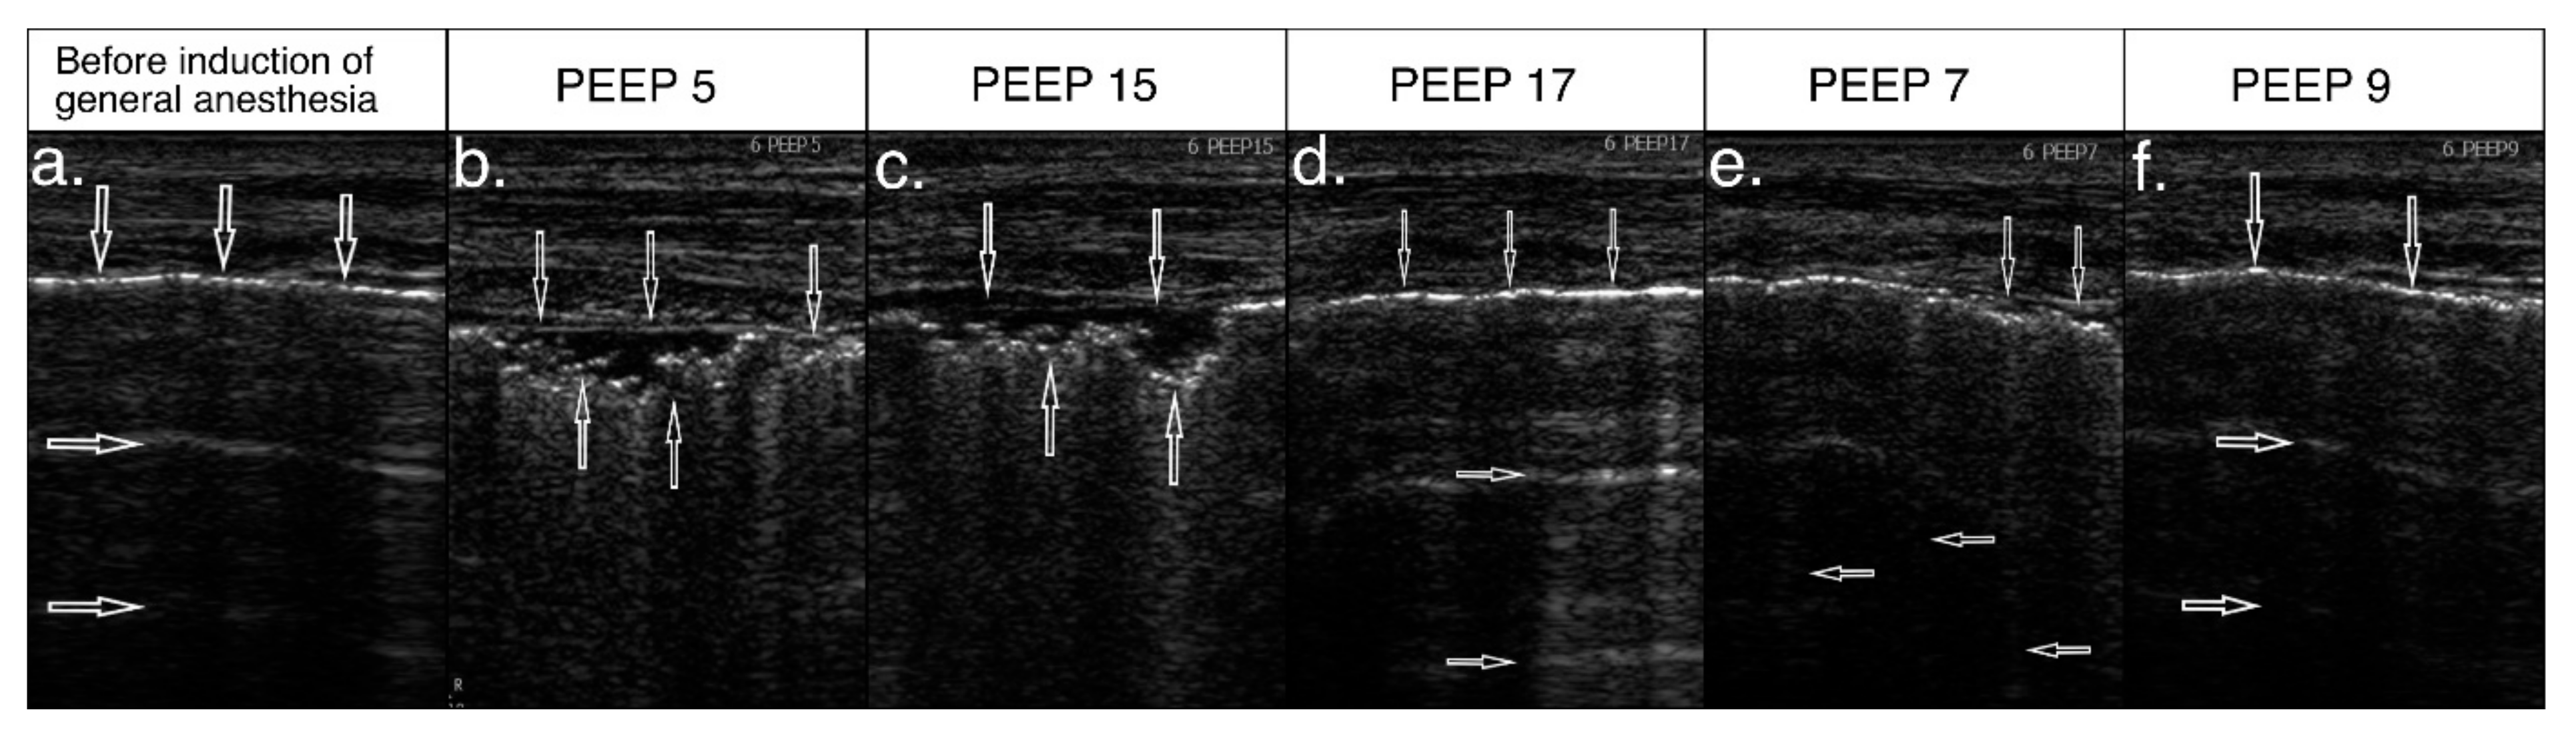

3.4. Effect of Ultrasound-Guided Recruitment Maneuver